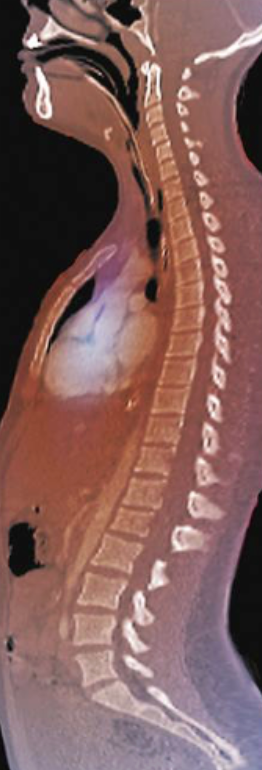

kyphosis

Exaggerated thoracic curvature

Ex. hunch back